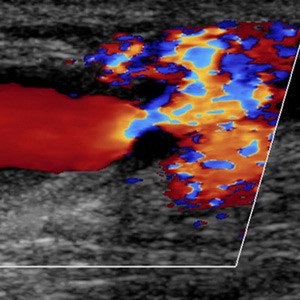

Ecografie Doppler - este o metodă simplă, comodă și precisă pentru examinare non-invazivă a fluxului sanguin, care permite în timp real pentru a obține grafica, sunetul, precum și informații cantitative a obiectului studiat. Efectuarea procedurii nu produce nici un disconfort pentru examen. Tot ceea ce se cere de la el - trebuie doar să se întindă în jos, în timp ce persoana calificată inspectează punctele de control corespunzătoare proiecția navelor dorite. Examinarea Doppler este la fel de eficient pentru ambele nave mici și mari. Poate fi realizat studii și arteriale și a vaselor venoase.

Această metodă face posibilă nu numai pentru a vizualiza vasele de sânge și țesutul moale din jur, dar, de asemenea, să efectueze un studiu de hemodinamica folosind coduri de Doppler color. Această metodă permite determinarea, chiar cea mai mică abatere de la normă.